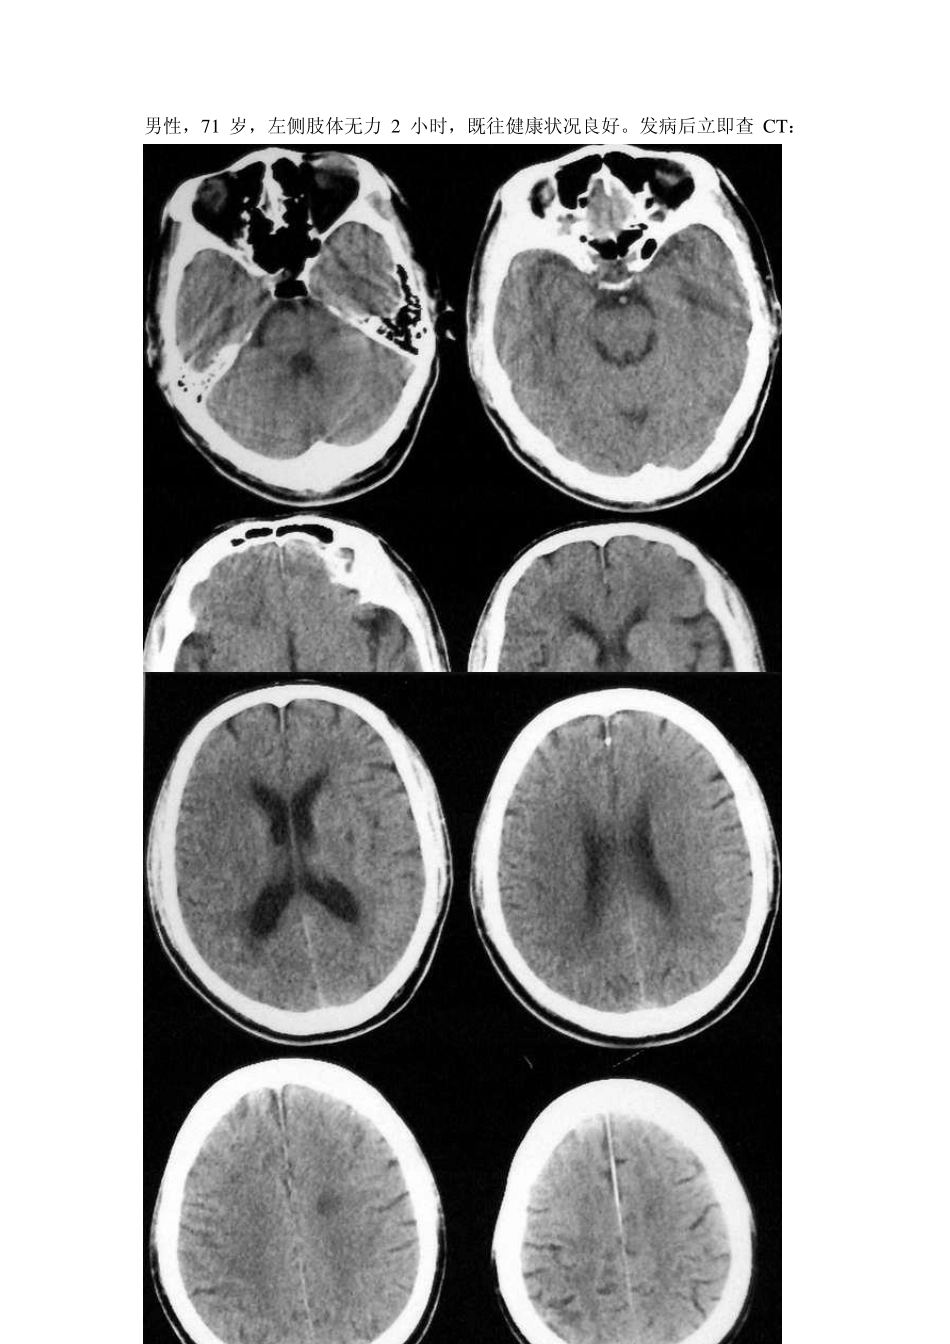

男性,71 岁,左侧肢体无力2 小时,既往健康状况良好。发病后立即查 CT: 从这两张片子看,都没有很明显的病灶,但仔细看可见右侧颞顶叶片状低密度影,脑沟回模糊、皮髓分界不清,1 天后复查 CT: 所谓的超急性脑梗死(临床根据发病时间,目前认为为6H 以内)在病理学上是脑细胞毒性水肿时期。此时,血脑屏障完整。在影像学上要注意有无脑局部肿胀的表现。CT:注意双侧脑沟是否对称,双侧内囊和外囊是否清晰可见,岛叶与外囊是否可以区分。MR:T1W I 上要注意双侧脑沟是否对称,脑回是否有增粗表现。此外还要注意血管是否异常。图 1-2 为超急性期CT 表现。病变在那一边?图 3-4 为MR 的T1W I 和 T2W I,你能看到局部脑肿胀么? 图 1 图 2 图3 图4 图1:左侧外囊与岛叶分界不清。图2:左侧脑沟明显变浅。图3:左侧岛叶盖部的脑回可见增粗;图4:左侧外侧裂内的血管流空影消失。上述表现为超急性期脑梗死的表现。病理基础为细胞毒性水肿。 脑梗塞早期的CT 征象: 1、动脉高密度征(致密动脉征):表现为一段动脉密度增高,CT 值高于正常动脉,而低于动脉粥样硬化斑,其形成机制商不清,主要见于大脑中动脉及其主要分支,其次是椎-基底动脉。 2、岛带征:脑岛灰质、白质界限模糊,呈均一的淡的密度影。 3、豆状核征:豆状核轮廓模糊,密度与脑白质一致或稍低。 4、皮质征:皮质局限性密度减低,与脑白质密度一致。 5、早期低密度改变。 6、占位效应。 以上表现多与脑动脉闭塞后引发的细胞内水肿和血管源性水肿有关,属非特异性表现,其中豆状核征、岛带征、皮质征及早期低密度改变是诊断早期脑梗塞的可*指征,动脉高密度征、占位效应不能单独作为诊断依据。 另外:诊断时需密切结合病史、病征。梗塞灶的CT 表现时间的早晚,除与CT 分辨率和诊断水平有关外,还取决于梗塞灶的大小、部位和缺血程度等。 豆状核征: 左偏瘫1.5 小时,CT 平扫示右侧豆状核密度降低与白质一致 2 天后复查,右侧豆状核区明显低密度影 岛带征: 左偏瘫5 小时,CT 平扫右侧脑岛带区灰质密度降低与白质一致 33 小时后复查,脑岛带区程明显低密度影 皮质征: 偏瘫5 小时,CT示右额颞皮质呈楔形密度减低与白质一致 A 71 岁男性左大脑中动脉梗塞后1.5 小时CT所见。示左岛带消失。(有尾箭头)与正常的右侧岛带对比(三角箭头)。左豆状核似乎正常。 B CT后马上进行左颈动脉造影,示左大脑中动脉M2 段栓子闭塞(有...